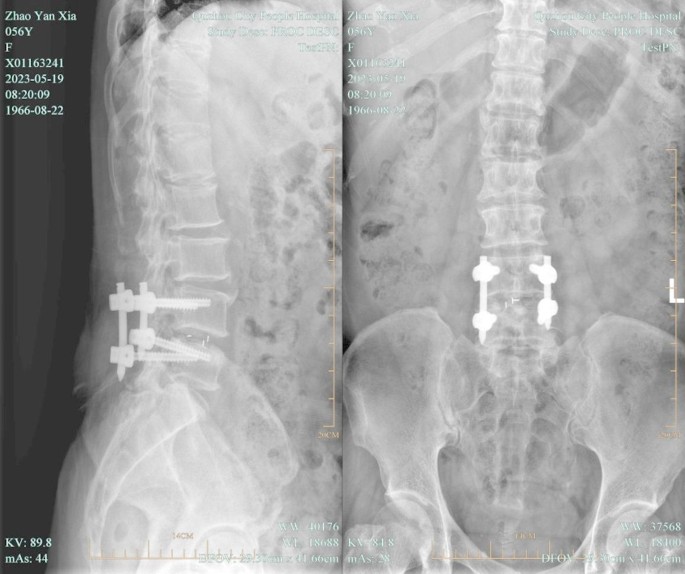

Patients in the experimental group received UBE-assisted interbody fusion surgery. After being given general anesthesia, the patient was positioned prone. The surgical site was identified using C-arm fluoroscopy by projecting the pedicle’s body surface on both sides of the waists 4 and 5. Standard cleaning and sterile sheeting were then carried out. Based on the indicated points, lateral puncture of the pedicle was done. Fluoroscopic examination of the puncture needle’s location during the procedure was necessary to determine whether it was at the vertebral arch’s pedicle. Following confirmation, the guide wire could be placed. The operation and observation channels could be built by making a double incision along the left side to introduce the skin expander. It was necessary to insert a 30° arthroscope into the observation channel after connecting the light source. Following a clean removal of the surrounding soft tissue in the work channel, adequate hemostasis was achieved with the use of a radiofrequency knife. The field of vision was exposed to the lower edge of the L4 vertebral plate and the higher edge of the L5 vertebral plate. To expose the dura mater and nerve roots in the visual field, the lumbar 4 lamina was removed from the ligamentum flavum insertion point, the upper edge of the lumbar 5 lamina and part of the facet joints of the lumbar 4/5 were removed, and the ligamentum flavum was also removed. Subsequently, protruding lumbar 4/5 intervertebral discs, as well as compressed posterior dura mater and nerve roots could be observed. The nerve roots were pulled apart using nerve stripping ions. The intervertebral disc was removed. The intervertebral space was processed to the upper and lower endplates. The bone graft bed was prepared. The protruding nucleus pulposus was retrieved with nucleus pulposus forceps. Hemostasis and intervertebral disc ablation were carried out with a radiofrequency knife, and the endplate was scraped off. After the intervertebral space was processed, the polyetheretherketone (PEEK) Cage was implanted. The size of the cage was selected according to the height (10–12 mm) and width (16–18 mm) of the intervertebral space measured by CT before operation. The cage was built with autologous bone, and the cage was high in anterior and low in posterior (sagittal lordosis Angle 5°) to maintain the physiological lordosis of the lumbar spine. Radiofrequency ablation hemostasis could be carried out once more when the nerve root had relaxed and the dura mater pulsation was found to be normal. After implanting autologous bone particles into the patient’s intervertebral space, an interbody fusion cage made of matched autologous bone was put in place. The arthroscopy could be removed once the fusion device was properly positioned during the fluoroscopy. The pedicle screw was then screwed along the guide wire, the round rod was positioned, and the screw plug was tightened and secured. The instruments and dressings could be counted once the C-arm fluoroscopy had confirmed the internal fixture’s position and proper length. A drainage tube could be inserted once it was determined that no mistakes had been made and the patient’s incision was not actively bleeding. Disinfection was performed again, and the incision was sutured. Patients in both groups were followed up for 3 months. The operation diagram was shown in Fig. 3. Lumbar spine images before and after surgery were shown in Figs. 4 and 5.

Images of the lumbar spine after surgery in a patient with LDH.